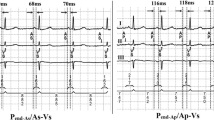

In Fig. 2, an overview of all electrical (ECG and VCG), mechanical (IVMD, SPS, and SRS), and hemodynamic (VTILVOT and SBP) parameters is presented as measured at different stimulation intervals for a representative patient of the AV group. When increasing the AV interval from 50 to 160 ms, the morphology of the ECG and VCG gradually changed, characterized by a decrease of QRS amplitudes and area. By further prolongation of the AV interval, these variables increased again, yet showing an opposite direction. IVMD started with earlier aortic ejection when applying LV pre-excitation, gradually becoming more synchronous and ending with earlier pulmonary ejection when loosing LV capture. With short AV intervals, there was considerable SPS, indicating passive early systolic septal stretch caused by early LV free wall activation, which gradually decreased and disappeared with longer AV intervals. SRS was absent during LV pre-excitation and increased with prolonging AV intervals. VTILVOT and SBP increased when increasing AV interval from 50 to 160 ms and subsequently decreased again.

Overview of the electrical, mechanical, and hemodynamic parameters at different AV intervals. A representative example of electrical, mechanical, and hemodynamic parameters while increasing the AV interval during LV pacing. From top to bottom: ECG in lead V2 (note that the value halfway in between LV pacing and LBBB is (−1.9 + 2.2) / 2 = 0.15), VCG in the transversal plane, pulsed wave Doppler signals over the pulmonary and aortic valve with values of the interventricular mechanical delay (IVMD), septal strain curves with values of systolic pre-stretch (SPS) and systolic rebound stretch (SRS; the interval within the vertical lines represents ystole), velocity time integral over the LV outflow tract (VTILVOT), finger blood pressure (FBP) measurements just before and after the transition from intrinsic conduction to a specific AV interval (for further explanation see text in “Methods”)